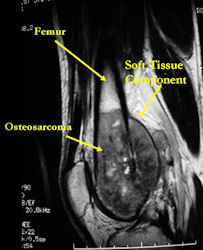

MRI with contrast (gadolinium) of the extremity Best for:

- determining intraosseous extent (size) of the tumor and size of the soft tissue component

- determining relationship of tumor to neurovascular structures

- detecting skip metastases

- Entire bone and adjacent joint should be visualized

- Most conventional osteosarcomas (90-95%) extend through the bone into the soft tissues and form a soft tissue mass outside of the bone